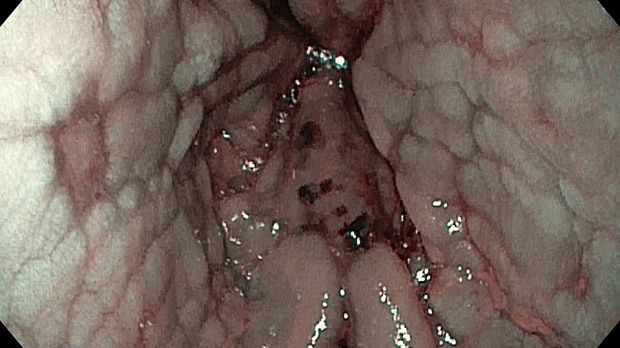

Публикации из социальных сетей: “Cobblestone esophagitis” (эзофагит со слизистой булыжной мостовой)

“Cobblestone esophagitis” (эзофагит со слизистой булыжной мостовой) - редкая эндоскопическая находка и ассоциируется с эозинофильным эзофагитом, кандидозом и пищеводом Барретта у взрослых. Он также может быть найден при тяжелом рефлюкс-эзофагите, вторичен к дистальной обструкции гастроинтестинального тракта. В нашем случае - это пациент после с 9-летним стажем бандажирования кардиального отдела желудка, признаками дуоденостаза, фундальной эрозивной гастропатией, расширением пищевода и уровнем жидкости в нем при горизонтальном положении, грыжи ПОД, эрозивно-язвенном дистальном эзофагите.. Пациент просто пришел удалить полип в прямой кишке и заодно посмотреть, что творится в желудке.... Ацетообеление+NBI+биопсия. ИПП на 3-4 мес и повтор для решения о Барретте.